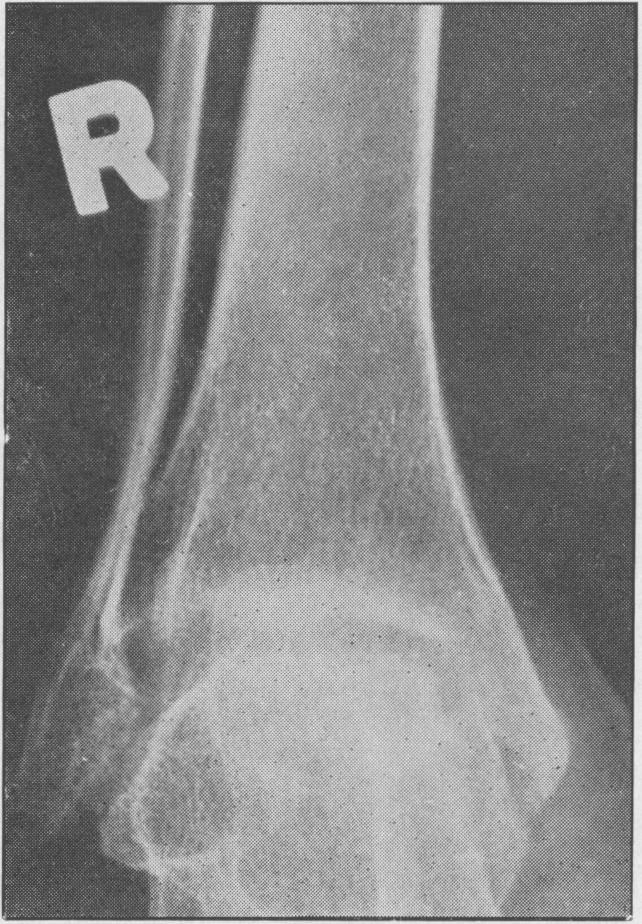

Juvenile rheumatoid arthritis (Still's disease).